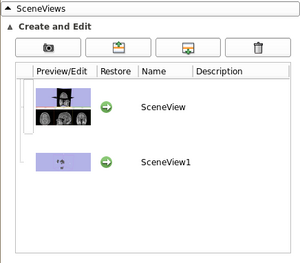

| qMRMLColorTableView |

|

A table view to display a color table model |

| qMRMLColorTableComboBox |

|

a tree combobox to choose a color table node |

| qMRMLThreeDViewsWidget |

|

a toolbar to control 3D views |